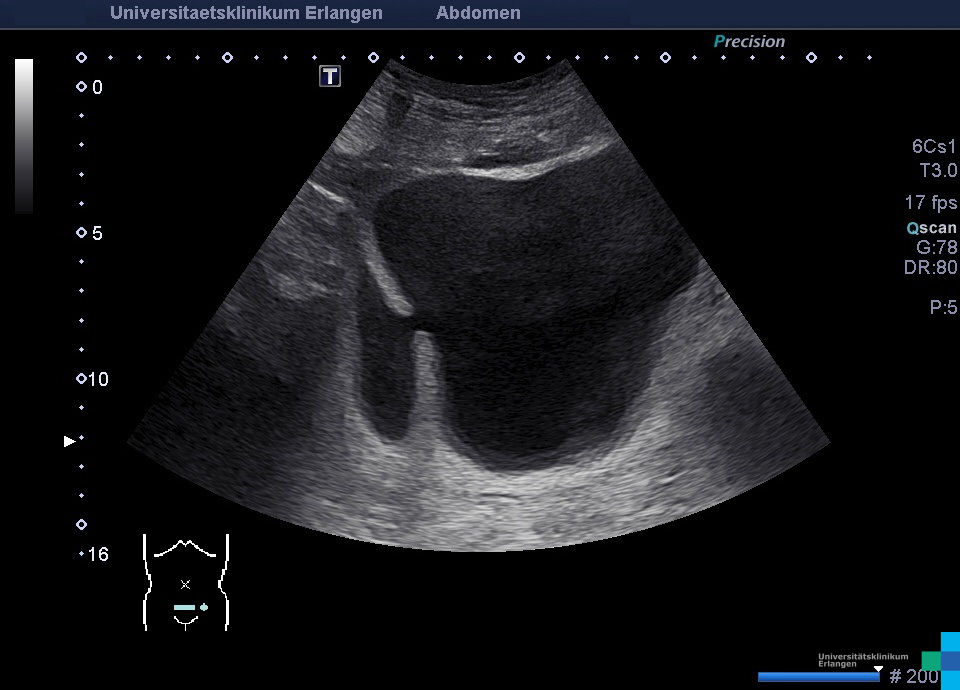

UBA_HBL_HBD_117.jpg